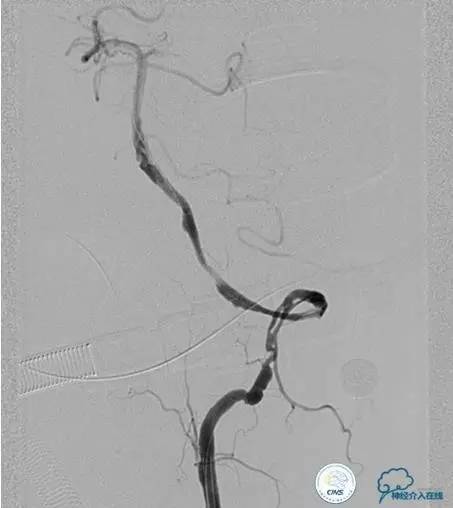

▼术前DSA

▼术中DSA

▼术后DSA